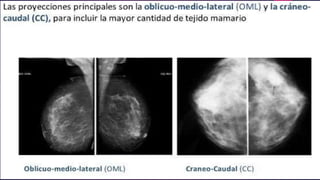

Las proyecciones

complementarias:

 Son aquellas que a criterio del radiólogo se realizan para ver

mejor una imagen o zona adyacente a la mama que no

quede incluida en la imagen principal (axila, cola de mama,

pliegue intermamario).